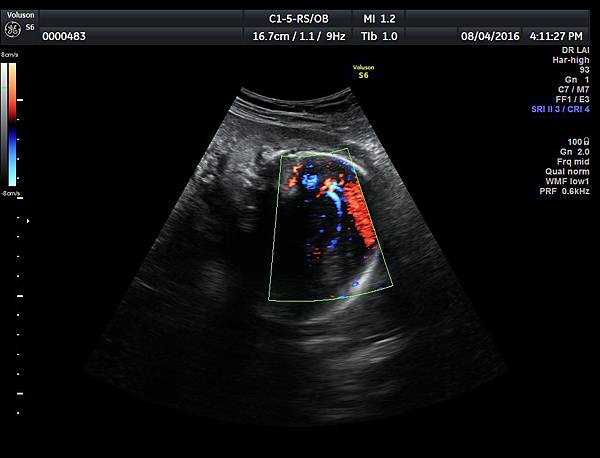

2016年8月4日在執行胎兒高層次超音波檢查時,我發現胎兒腦部的CSP(cavum septum pellucidum)很不清楚(附圖1~4),遇到這種情況,需要仔細評估胎兒腦部的駢胝體,因為CSP的天花板是駢胝體,CSP不明顯時,要合理的懷疑駢胝體沒有發育,或駢胝體下方有長東西(例如lipoma),駢胝體是連接左右大腦的神經纖維所組成。

1. 矢狀切面(sagittal plane):駢胝體呈現類似三明治的中間黑色部分,上面一層薄薄白色的區域是callosum sulcus,打上flow可以看到pericallosum artery在駢胝體上面的周圍,pericallosum artery來源是前腦動脈,參考附圖 6~10,三明治下面白白的部分是和CSP做比較得到的,如果這一層長lipoma(附圖 5),CSP很可能看不到。